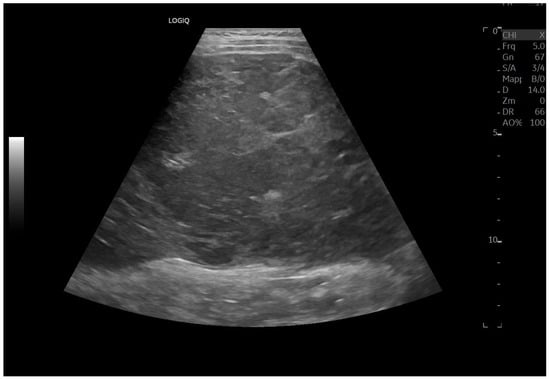

Abdominal ultrasound is a fundamental diagnostic tool in clinical practice, due to its availability, safety, and overall accuracy. This Special Issue will delve into the most recent technological and methodological innovations in abdominal ultrasound imaging, offering readers a comprehensive overview of advanced techniques, specific clinical indications, and solutions to emerging challenges. Among the various topics, it will cover the use of high-resolution probes, the integration of elastography for assessing liver fibrosis, and the application of contrast-enhanced ultrasound for identifying complex lesions. Strategies for training and professional development will also be examined to improve ultrasound performance and result interpretation.